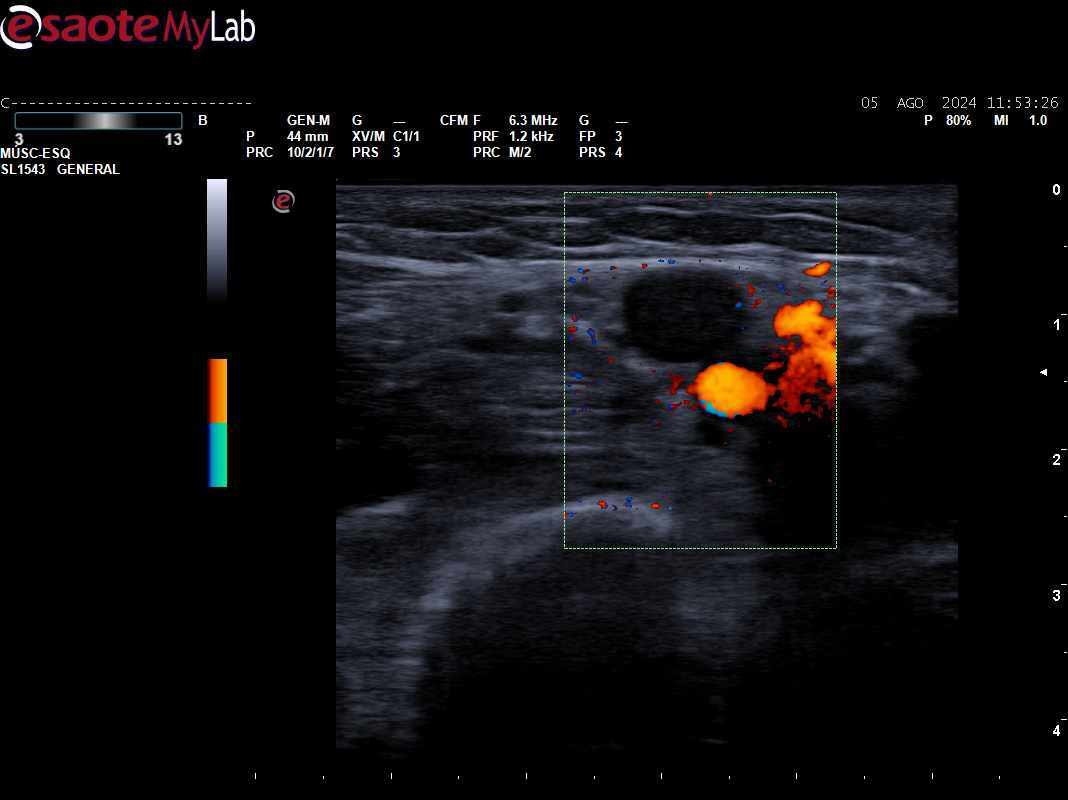

Descripción de los hallazgos ecográficos y las imágenes más relevantes para la resolución del caso

Se objetiva ausencia de compresibilidad y señal Doppler con material hiperecogénico intraluminal compatible con trombosis en territorio braquial de MSI.